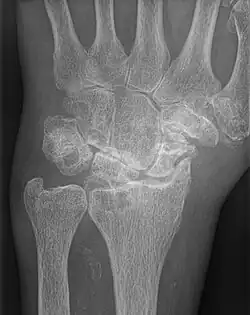

AP wrist x-ray demonstrating Stage III scapholunate advanced collapse | |

Stage III SLAC wrist

Stage III SLAC wrist involves the entire radioscaphoid joint and the capitolunate joint.[3] The PA wrist x-ray will demonstrate sclerosis and joint space narrowing between the lunate and capitate. Over time, the capitate will migrate proximally into the space created by the scapholunate dissociation.[2] The radiographic findings in Stage III SLAC wrist are synonymous with the Terry-Thomas sign, indicating complete scapholunate dissociation.[2]